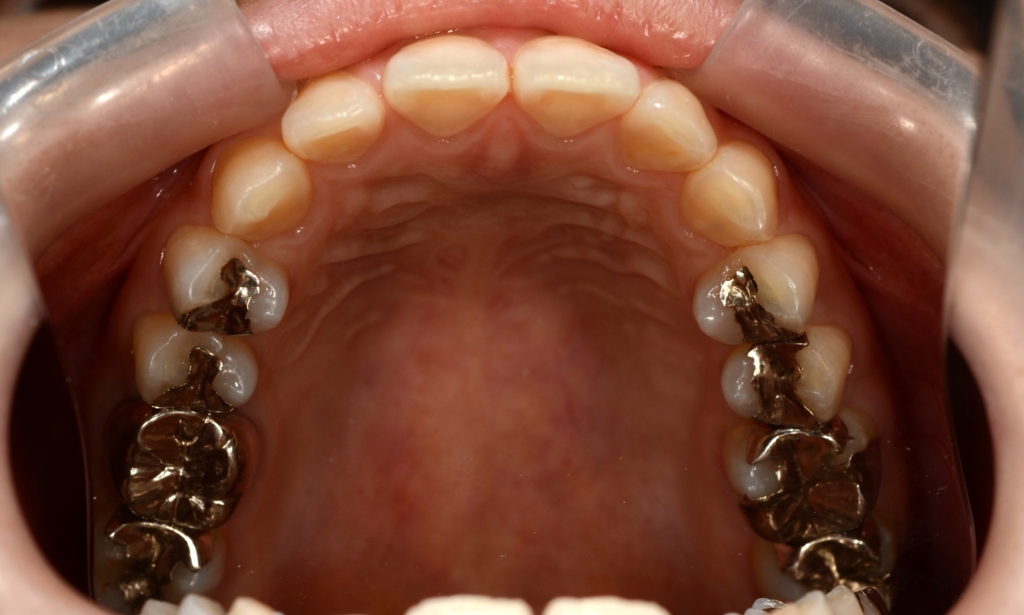

【治療装置】

マルチブラケットシステム(スタンダードtype)で矯正を開始

アンカースクリュー:

上顎に計6本(前歯に2本、奥歯に2本、口蓋に2本)使用

部位は、上顎の口蓋の真ん中、臼歯部(左右側とも)と前歯部の頬側、になります。